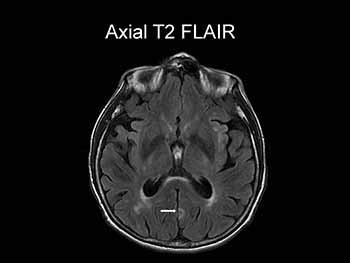

Appropriate studies are obtained. EEG is reported as "Normal awake study. No epileptiform discharges seen." MRI of the head without contrast is shown:

Which of the following is a correct interpretation of this patient’s MRI? (You may select only one option.)